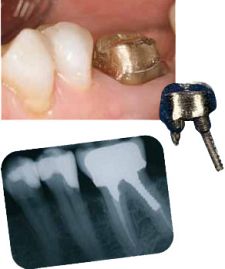

Sådan ser tanden ud, efter at den er slebet til.

Tanden – nu med en guldkrone på.

Tanden har fået en guldopbygning. Nu kan tanden bære en krone.

Er din tand rodbehandlet, og mangler der meget af den, er det ikke muligt at få en krone til at sidde fast. Så kan det være nødvendigt først at fremstille en opbygning, der sidder fast i roden med en stift. Kronen kan så sættes fast på opbygningen.

Før du kan få lavet en krone, skal din tand slibes til. Dernæst skal der tages et aftryk af tanden.